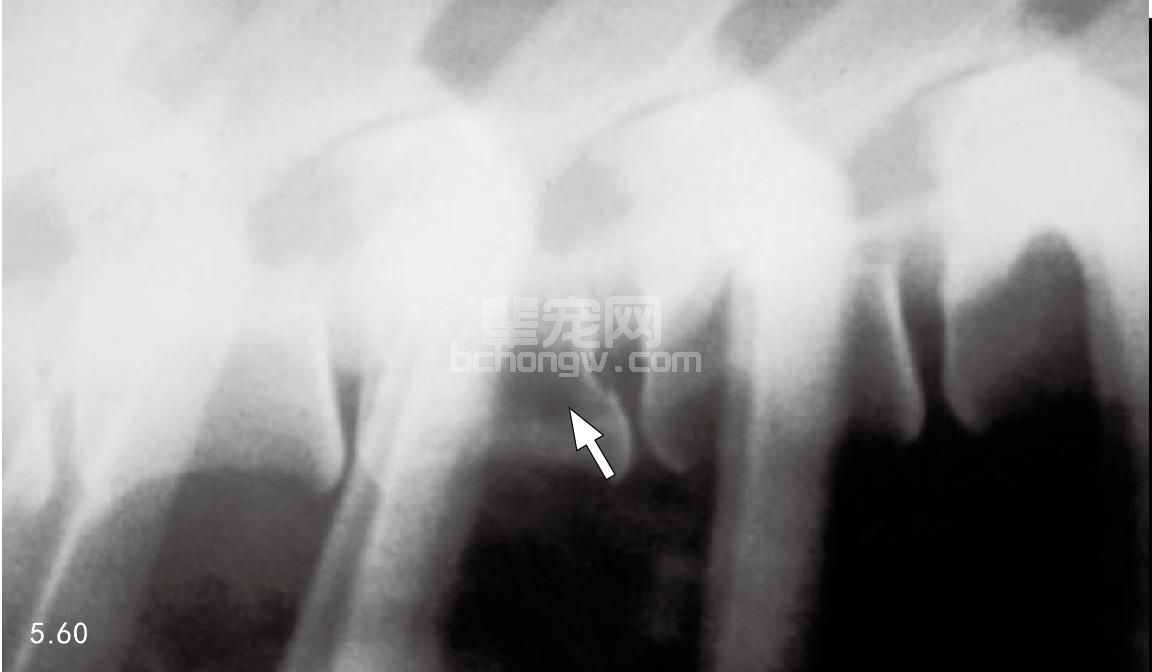

图5.59~图5.61 犬转移性前列腺腺癌的颈椎和胸椎的X线片和闪烁扫描图。图5.59颈椎椎体透射线区域(箭头所指)。图5.60胸椎椎体X射线区域(箭 头所指)。图5.61对同一只犬做的闪烁扫描,显示的“热点”为转移部位。